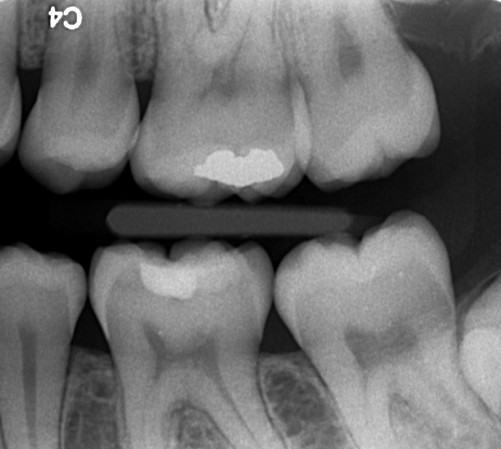

Farvestoffer til afsløring af plak på tænderne. Selv efter tre uger uden tandbørstning er der plakfri områder. Et område uden plak er et cariesfrit område. Med regelmæssig brug af tandbørste og tandtråd er det muligt helt at fjerne cariestruslen. Kun steder hvor plakken ikke fjernes regelmæssigt kan der opstå caries. I naturen er det den grove kost der fjerner plakken. Glatte tandoverflader er en evolutionær genistreg, der letter plakfjernelsen på de flader der udsættes for mindre slid. Formålet med regelmæssig plakfjernelse er at få fjernet plakken fra de tandoverflader, hvor almindelig tygning ikke fjerner plakken (plak-stagnations-områderne). (Else Theilade).